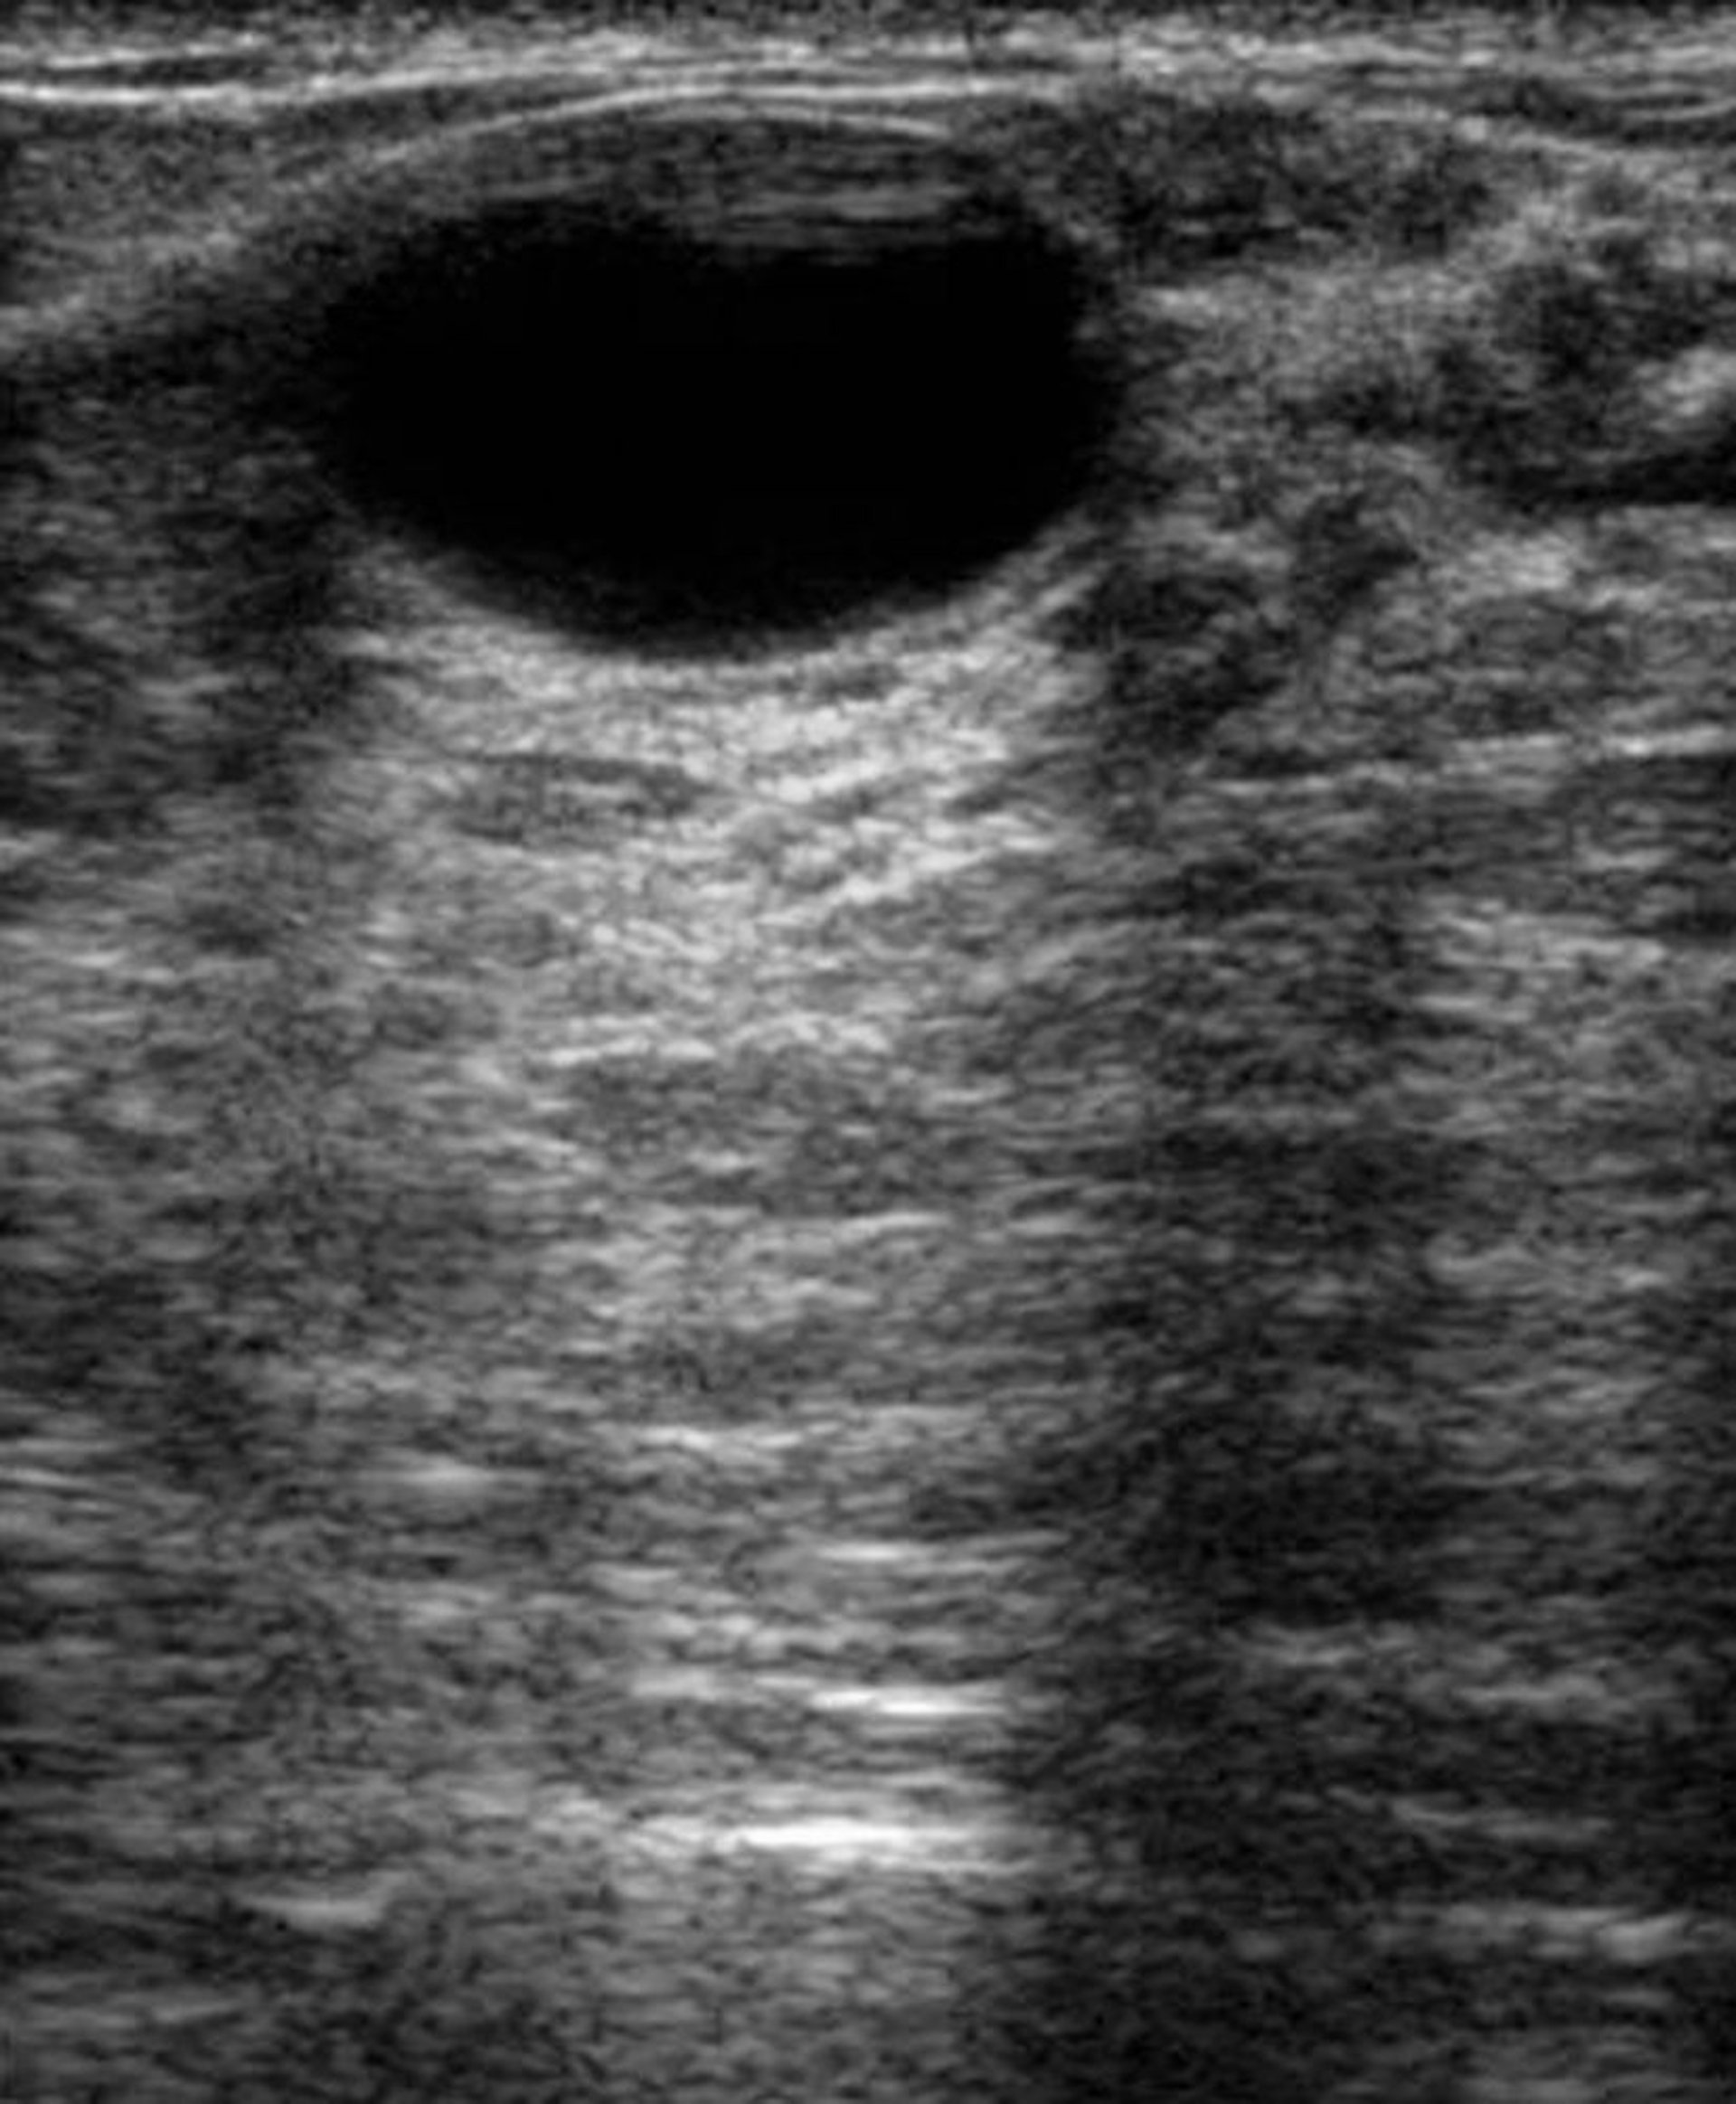

Cette échographie du sein d'une patiente atteinte d'une maladie fibrokystique montre un kyste en haut au centre. Les kystes sont des poches remplies de liquide et sont habituellement bénins.

DR NAJEEB LAYYOUS/SCIENCE PHOTO LIBRARY